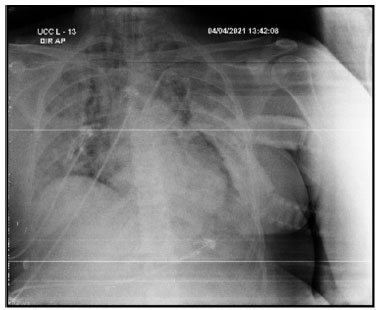

Após o início de VM invasiva, apresentou assincronias frequentes, dificuldade de manter parâmetros VM protetora, com necessidade de ajustes frequentes no ventilador e de associar sedativos em altas doses e bloqueador neuromuscular (fez uso de midazolam, propofol, fentanil e pancurônio). Exame de imagem após intubação orotraqueal, mostrava cânula endotraqueal bem-posicionada, opacidades parenquimatosas difusas, cateter venoso central à direita e sem sinais de pneumotórax (vide figura A). Entretanto, no dia 05/04/21 paciente apresentou ao exame físico enfisema subcutâneo extenso em região torácica e cervical, realizou exames de imagem que evidenciaram extenso enfisema subcutâneo e moderado pneumomediastino (vide figuras B e C). Discutido caso com equipe de cirurgia torácica que optou por manter tratamento conservador e não realizar procedimentos invasivos, como drenagem de subcutâneo.